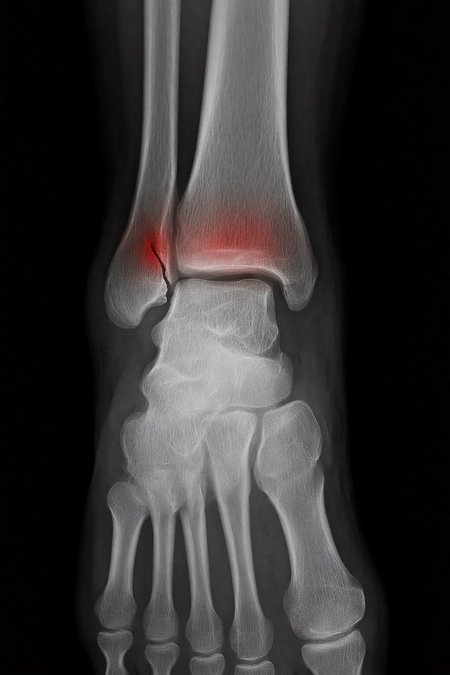

Can a model like Flux Kontext, designed for editing art and photography, be used to work with medical images, for example, with something 'as simple' as red-marking fractures?

The quick answer: it does do something interesting, but it over-scores and is far from reliable as a medical tool. It's a prototype to play with the idea, nothing more.

2. Ask: “Make marks where there is a fracture”.

Test results:

False positives ≈ 24%

Fracture detection ≈ 20%

False positives ≈ 80%

Fracture detection ≈ 86%

Even more aggressive settings (e.g. rk beta57 to denoise 1.0) reach the absurd: 100% false positives and 100% detection: it paints everything red and almost hits all fractures beyond marking healthy areas, for an untrained eye.